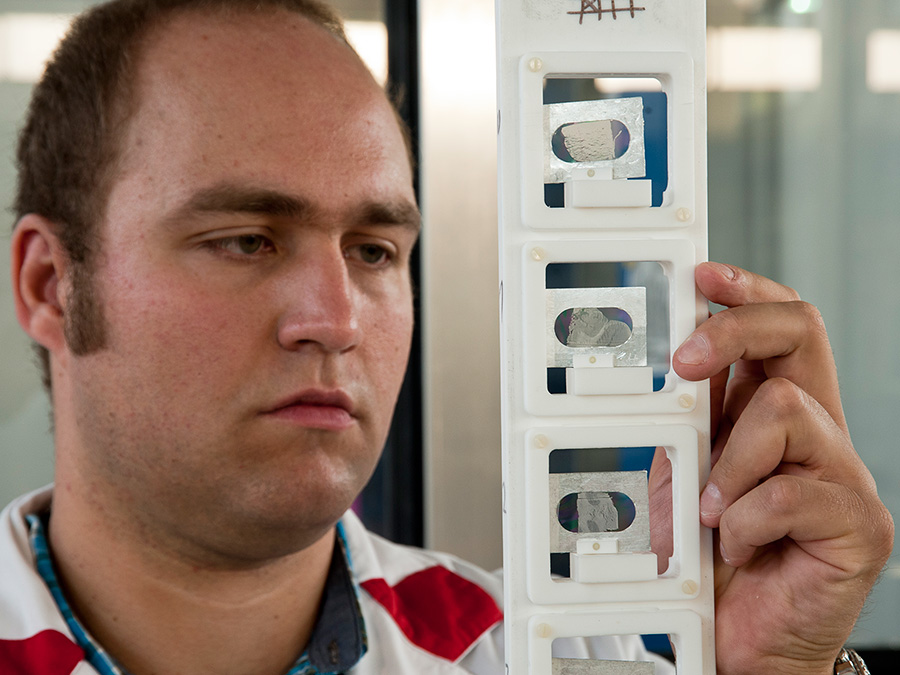

Dem geht nun Josef Lichtinger in seiner Doktorarbeit am Lehrstuhl für Physik der Hadronen und Kerne (E12) der TUM nach. Von der Rechtsmedizin der Ludwig-Maximilians-Universität München (LMU) erhielt er Gewebeproben von Patienten, die mit Lithium behandelt wurden, unbehandelten Patienten und gesunden Vergleichspersonen. Diese setzte der Physiker am Messplatz der Prompten Gamma Aktivierungsanalyse am FRM II einem fokussierten kalten Neutronenstrahl höchster Intensität aus.

Lithium reagiert sehr spezifisch mit Neutronen und zerfällt in ein Helium- sowie ein Tritiumatom. Mit einem speziellen Detektor, den Josef Lichtinger entwickelt hat, können deshalb so geringe Mengen wie 0,45 Nanogramm Lithium pro Gramm Gewebe gemessen werden. „So genau wie mit Neutronen kann man das mit keiner anderen Methode nachweisen“, sagt Jutta Schöpfer, Rechtsmedizinerin an der LMU, die mehrere Forschungsprojekte zur Lithiumverteilung im menschlichen Körper betreut.

Seine Ergebnisse erstaunen: Nur bei den Proben eines depressiven Patienten, der mit Lithium behandelt worden war, beobachtete Josef Lichtinger eine höhere Anreicherung des Lithium in der sogenannten weißen Substanz. Das ist der Bereich im menschlichen Gehirn, in dem die Nervenbahnen laufen. Der Lithiumgehalt in der benachbarten grauen Substanz war 3-4-fach geringer. Die Lithium-Anreicherung in der weißen Substanz konnte bei mehreren unbehandelten depressiven Patienten dagegen nicht beobachtet werden. Das weist darauf hin, dass Lithium nicht wie andere Psychopharmaka im Zwischenraum der Nervenzellen wirkt, sondern in den Nervenbahnen selbst.

Nun will Josef Lichtinger weitere Gewebeproben an der Forschungs-Neutronenquelle in Garching untersuchen, um seine Ergebnisse zu bestätigen und zu erweitern. Am Ende des Projekts steht eine Landkarte des Gehirns eines gesunden und eines depressiven Patienten, die ortsaufgelöst die Lithiumanreicherung zeigt. So könnte man das Universalmedikament Lithium zukünftig noch zielgenauer und kontrollierter gegen psychische Erkrankungen einsetzen. Die Arbeit wird von der Deutschen Forschungsgemeinschaft (DFG) unterstützt.